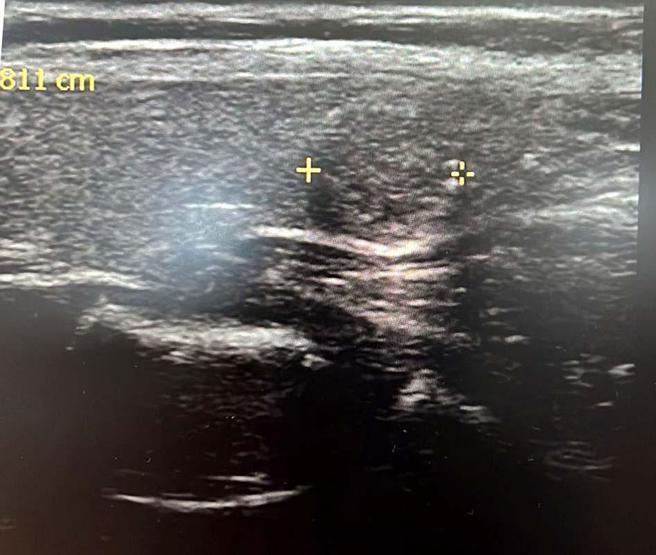

Endokrinoloji ve Metabolizma Hastalıkları Uzmanı Dr. Ahmet Suat Demir, tiroit nodüllerinin oluşumundaki en yaygın nedenin iyot eksikliği olduğunu belirterek, "Tiroit nodülleri; iyot eksikliğinin olduğu endemik bölgelerde, toplumun yaklaşık yüzde 15’inde görülebilmektedir. Kadınlarda yaygın olmakla birlikte, çevresel ve genetik faktörler tiroit nodül riskini de artırmaktadır" dedi.

Tiroit nodülü vakalarında son yıllarda artış yaşandığı gözlenirken, uzmanlar, bu artışın en yaygın sebebinin iyot eksikliği olduğuna dikkat çekiyor. Ses kısıklığı, yutma güçlüğü ve nefes darlığı gibi belirtilerle ortaya çıkabilen nodüller, artan farkındalık ve ultrason sayesinde semptomsuz hastalarda da saptanabiliyor. Nodüllerin yüzde 10 ila 20’sinin kötü huylu olabileceğini, düzenli takip ve erken teşhisin büyük önem taşıdığı belirten uzmanlar, sigara kullanımı ve genetik yatkınlığın risk faktörleri arasında yer aldığını belirtirken, özellikle kadınlarda tiroit kanseri görülme oranının daha yüksek olduğunu vurguluyor.

Endokrinoloji ve Metabolizma Hastalıkları Uzmanı Dr. Ahmet Suat Demir, tiroit nodülü vakalarının besinlerdeki iyot eksikliğinden kaynaklandığını belirterek, “Tiroit nodüllerinin oluşumunda en sık karşılaştığımız neden iyot eksikliğinin olmasıdır. Tiroit nodülleri; iyot eksikliğinin olduğu endemik bölgelerde, toplumun yaklaşık yüzde 15’inde görülebilmektedir. Kadınlarda yaygın olmakla birlikte, çevresel ve genetik faktörler tiroit nodül riskini de artırmaktadır. Tiroit nodülleri büyüdüğünde 'bası bulgusu' ile kendini belli eder. Belirtileri ise ses kısıklığı, yutma güçlüğü, nefes darlığıdır. Boğazınıza dokunduğunuzda elinizde nodülü hissetmeniz ile de varlığını anlaşılabilir. Tiroit nodülü oluşumunda, Doğu Karadeniz Bölgesi'nde lahana tüketimi suçlanmaktadır. Fakat bunun sebebi besinlerdeki iyot eksikliğidir" dedi.

Tiroit nodülü tespitinde farkındalığın artığını ifade eden Dr. Demir, "Nodül tespitindeki farkındalığımız arttı. Tiroit ultrasonu kullanıyor olmamız da bu artışa etken oldu. 'Bası bulgusu' ile dokunarak muayene ettiğimizde; mevcut olan nodüllerin yaklaşık yüzde 20’sini tespit edebiliyoruz. Nodüllerin birçoğunun özelliklerini ve boyutlarını ise tiroit ultrasonu ile tespit ediyoruz. Son dönemlerde vakalarda artış var. Bazen hiçbir semptomu olmayan hastalarda da tiroit nodülleri tespit ediyoruz. Nodülleri özelliklerine göre değerlendirerek gerekli hastalardan biyopsi alıyoruz. İyi ya kötü huylu nodüle göre tedavi uyguluyoruz. Nodülü belli aralıklarla takip ediyoruz. Tiroit nodüllerinin yüzde 10 ila 20 kadarı kötü huylu olabiliyor. Birçok kanser türü erkek hastalarda fazla görülürken, özellikle tiroit kanseri sıklığı kadın hastalarımızda daha yüksektir. Kadın hastalar daha sık muayeneye geliyor ve farkındalıkları daha yüksek" diye konuştu.